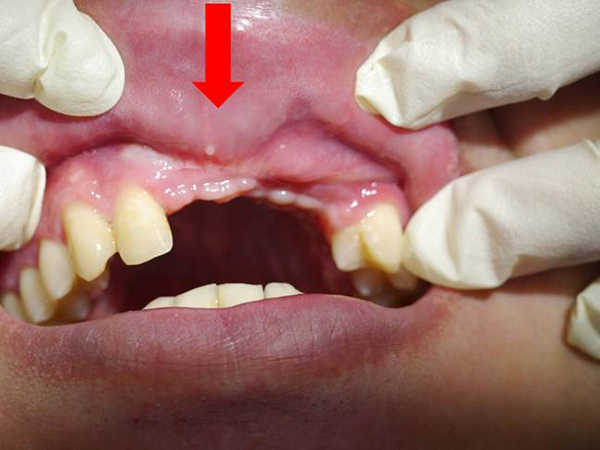

車禍後,前庭加深手術合併疤痕組織移除+游離牙齦移植覆蓋+雷射輔助修復正常組織案例

| 治療前(紅色箭頭) : 嚴重疤痕組織增生,導致牙齦組織攣縮, 嘴唇無法正常閉合,刷牙不舒服, 也無法製作正式假牙。 ![]() |

治療後(黃色箭頭) : 前庭恢復正常位置,嘴唇得以正常閉合, 疤痕組織移除後,可見新生血管組織, 可正常刷牙並製作正式假牙。 ![]() |